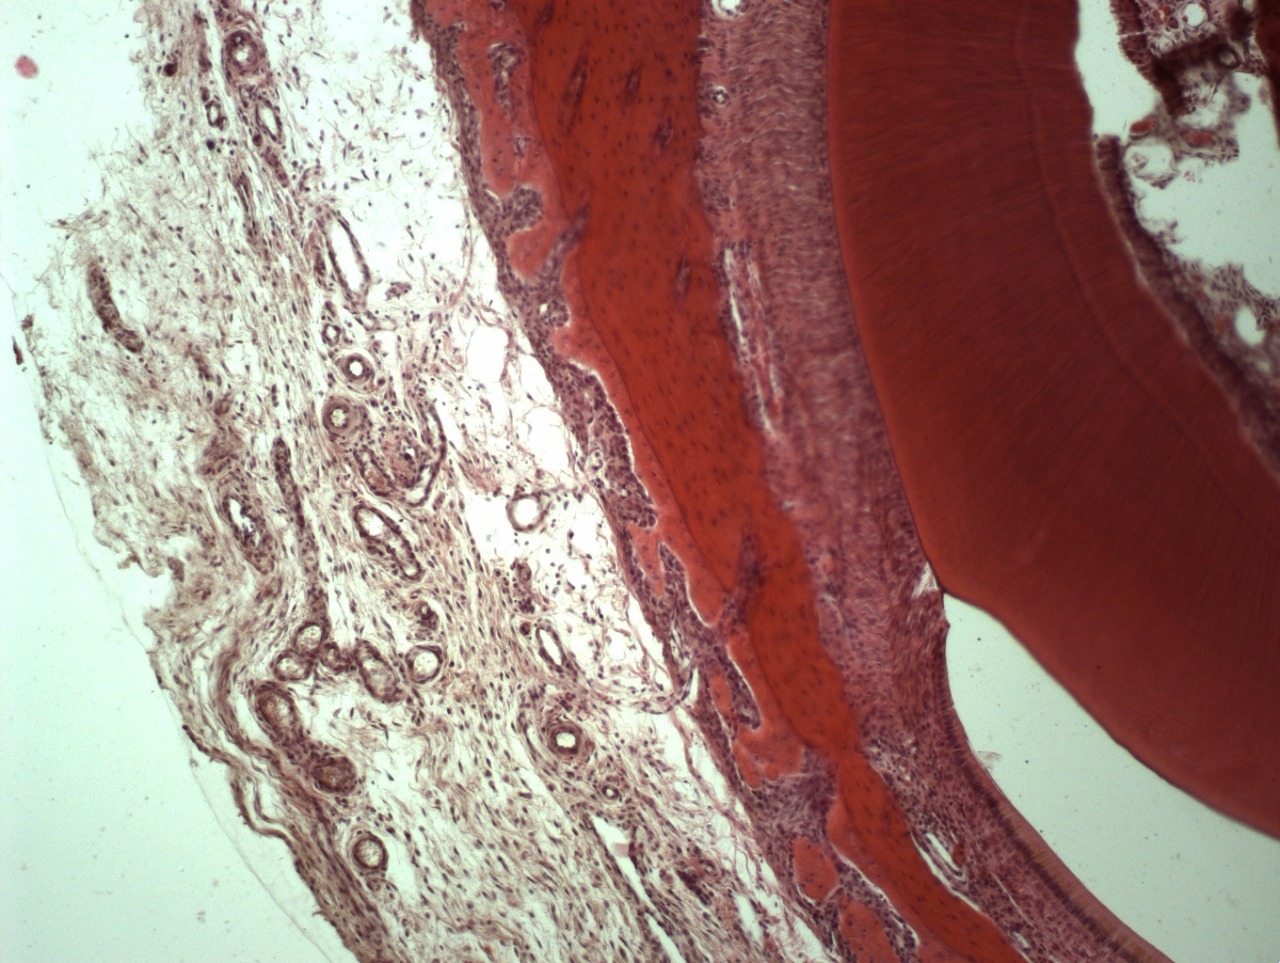

• Все материалы и препараты для стоматологии полностью резорбируются и замещаются собственными тканями на 100%.

• Например, таким образом удаляются все следы жира, белка, нуклеиновых кислот, мертвых клеток и их компонентов, неколлагеновых белков и прочих соединений. Вследствие такой очистки остается только коллагено-минеральный каркас мертвого межклеточного вещества костной ткани, состав которого стабилен на протяжении всей жизни человека.

• При последующей лиофилизации вся свободная и связанная влага испаряется из кости, и она [кость] немного сокращается в объеме, как бы «подседает», на 10-15%.